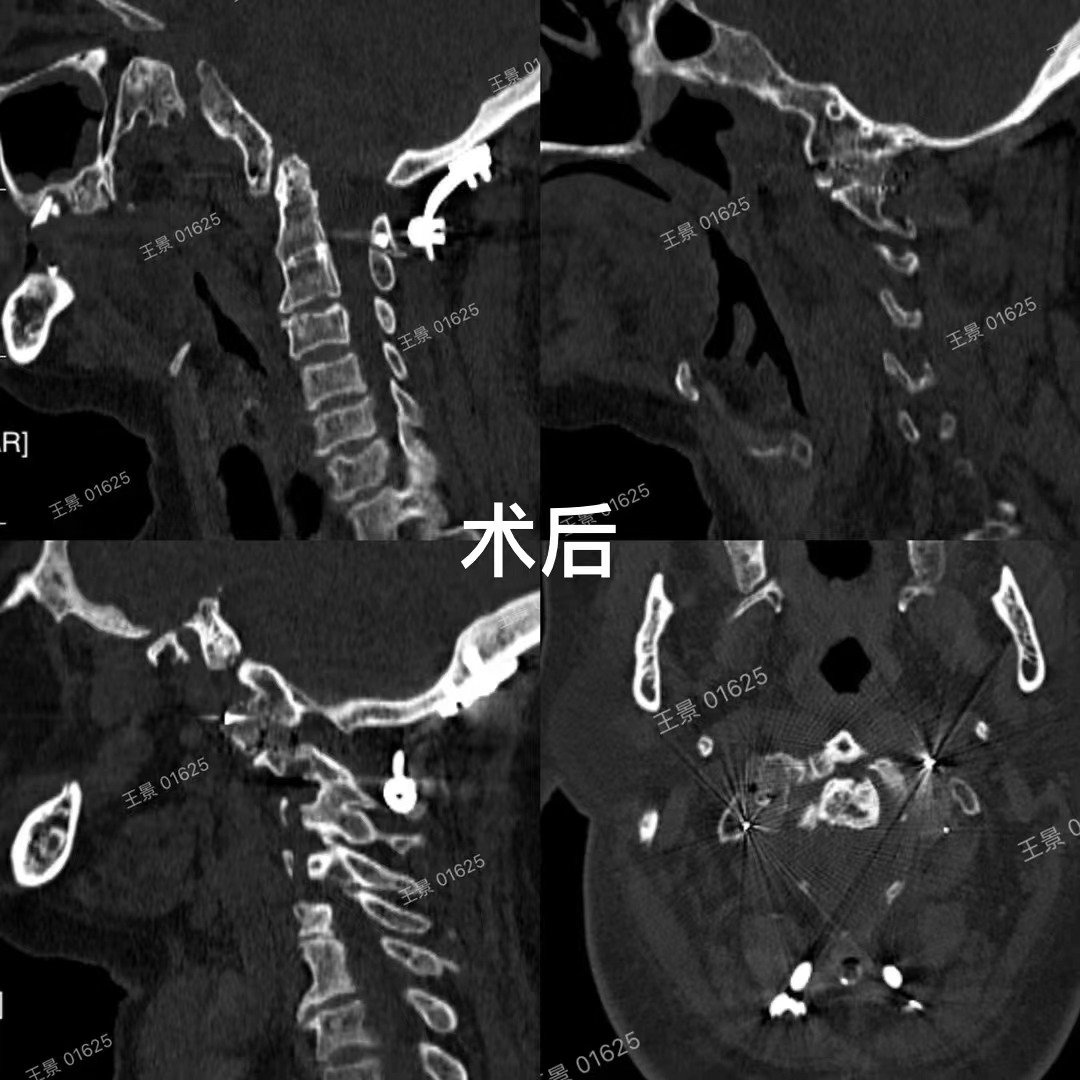

兰大二院骨科王景团队在既往治疗难复性寰枢椎脱位及颅底凹陷的经验和基础上,已完成多例显微镜辅助下难复性寰枢椎脱位的后路松解、椎间隙撑开复位融合技术,均取得良好效果。这项新技术在不需要外在牵引的情况下,使大部分难复性寰枢椎脱位得到了快捷安全有效的治疗,寰枢椎关节间融合也为颅颈交界区畸形手术提供了强有力支撑和有效融合界面。

此项技术也填补了我省此类技术的空白,相关手术病例进行多次学术示范交流,获得多位全国专家的一致肯定好评,有力助推医院上颈椎疾病诊疗水平处于全国先进水平。